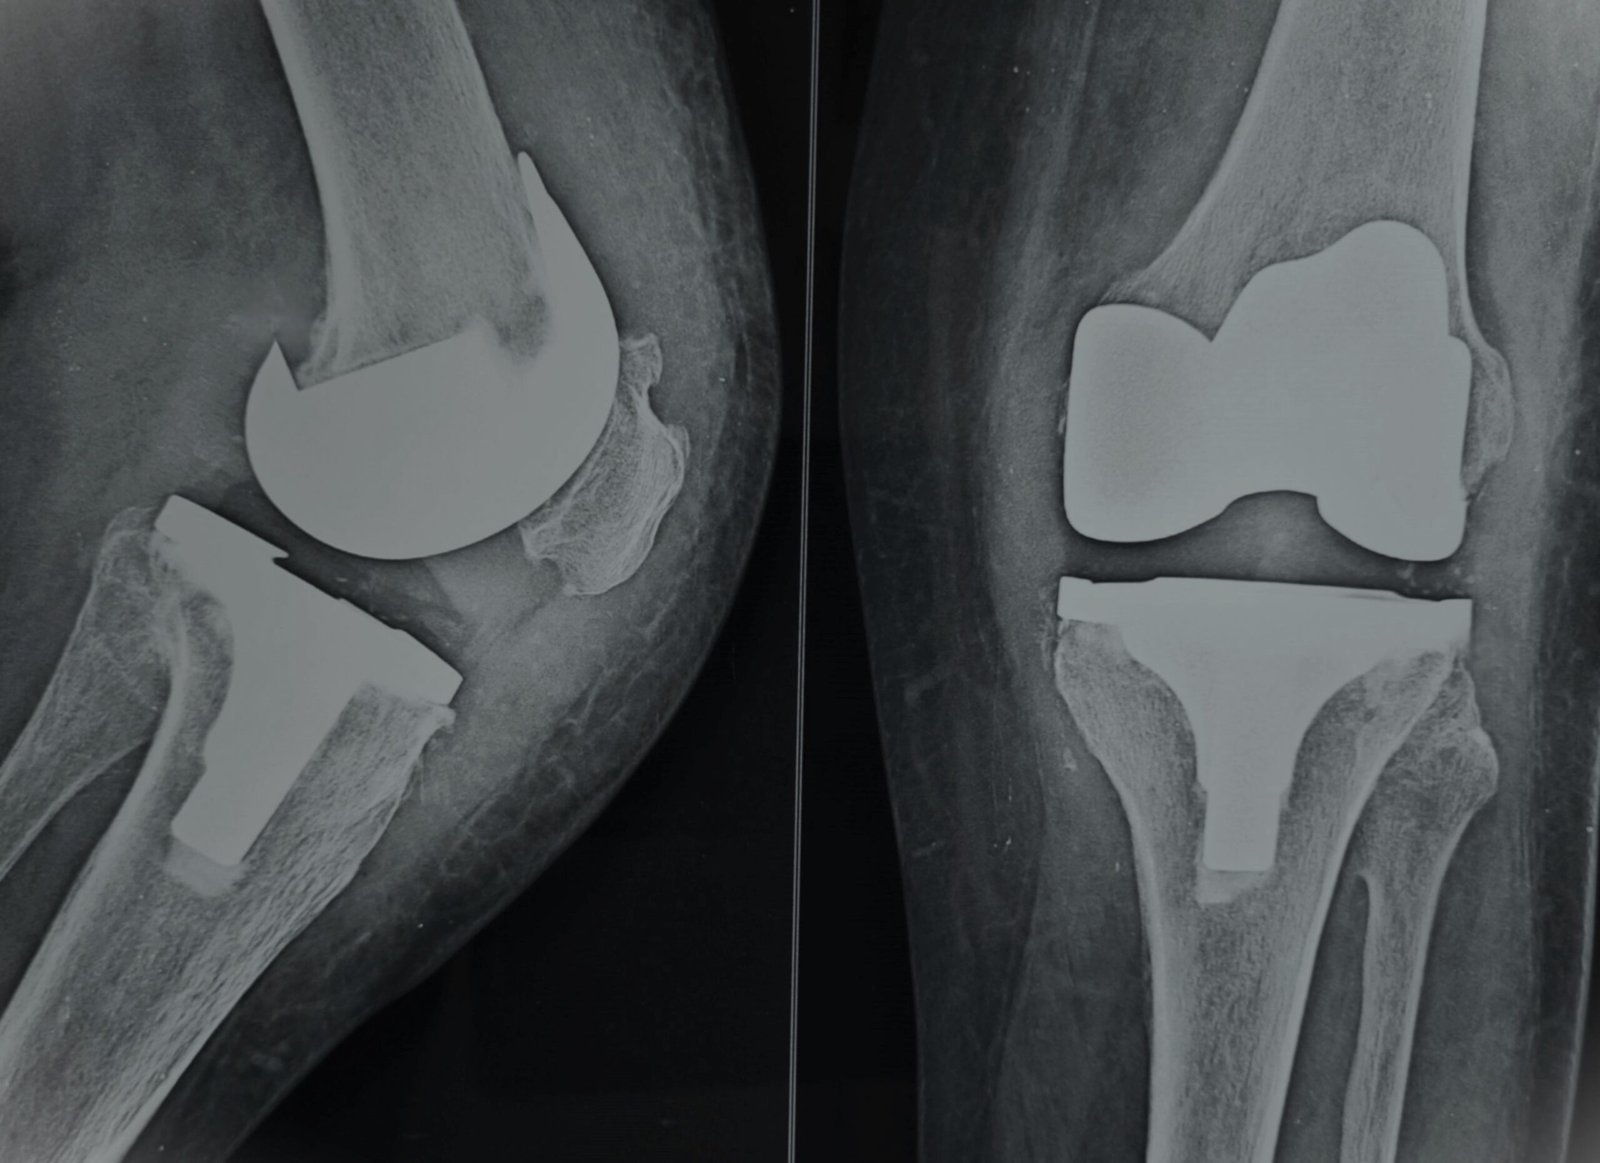

Post-Op Follow Up

Stiff Knee with Flexion Contracture & Rigid Varus